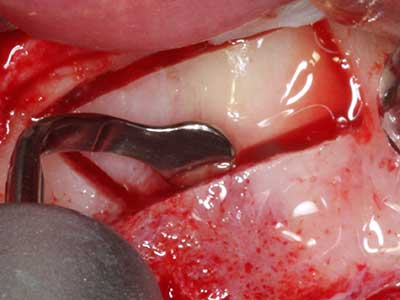

Piezo surgery has additional advantages when harvesting bone blocks. In addition to the high precision with osteotomy described above, the use of the thin saw tips specifically minimizes loss of material. Greater loss of material during harvesting can be expected with the thicker instrument tips, particularly when using Lindemann drills (Lakshmiganthan, Gokulanathan et al. 2012). The basal separation, which is necessary particularly for retromolar block transplants, is simplified by specially designed rectangular saws, with the result that piezo surgery is viewed as a precise, simple and safe procedure for harvesting retromolar bone blocks (Happe 2007) (Fig. 1-12).

When surgical procedures are performed on bone in the immediate vicinity of sensitive structures such as blood vessels or nerves, rotary instruments pose a significant risk of iatrogenic injury. Piezoelectric devices can be helpful for preparation of bone covers and removal of hard tissue close to nerves, particularly for exposure of nerves after iatrogenic injury but also during nerve lateralization for resective and reconstructive procedures or implant placement (Fig. 17-20). Light contact between the piezotip and the nerve does not generally result in damage but proceeding incautiously with saw-like motions or attachments where a residual bone substrate remains may cause temporary or even permanent nerve damage. However, the risk of damage is considered to be substantially lower than when using saws or milling instruments (Pereira, Gealh et al. 2014).